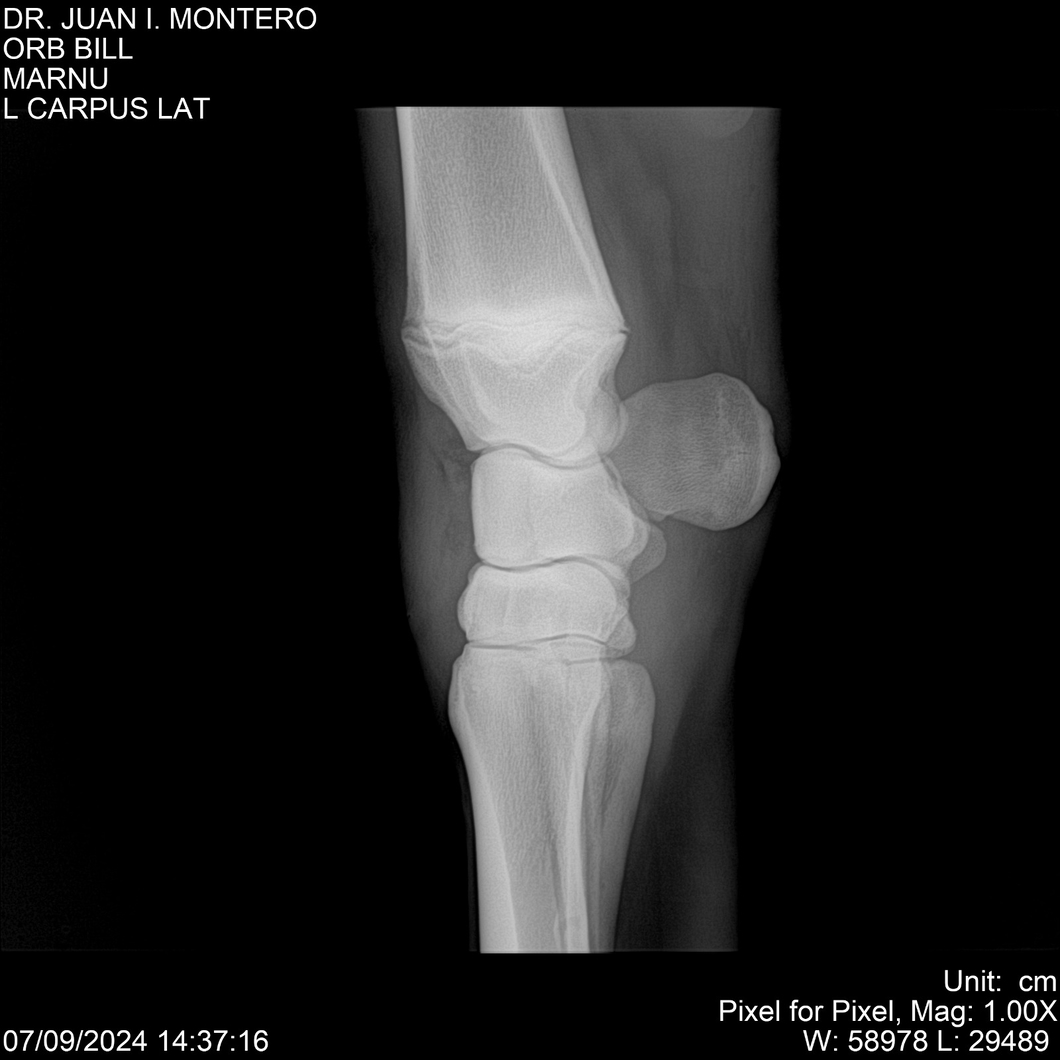

LOTE 7, ORB BILL 🔥 🔥 🔥 Lote Anterior Volver al remate Lote Siguiente Ficha Contacto Montevideo - Ficha del Lote Identificador: #282523 Categoría: Yeguarizos Montevideo - 83 Visualizaciones ClicData Contacto Empresa: Abelenda N. R., Walter Hugo Nombre*: Teléfono* : E-mail* : Mensaje Enviar Registrese gratis Este contenido Exclusivo está disponible sólo para usuarios registrados Ingresar